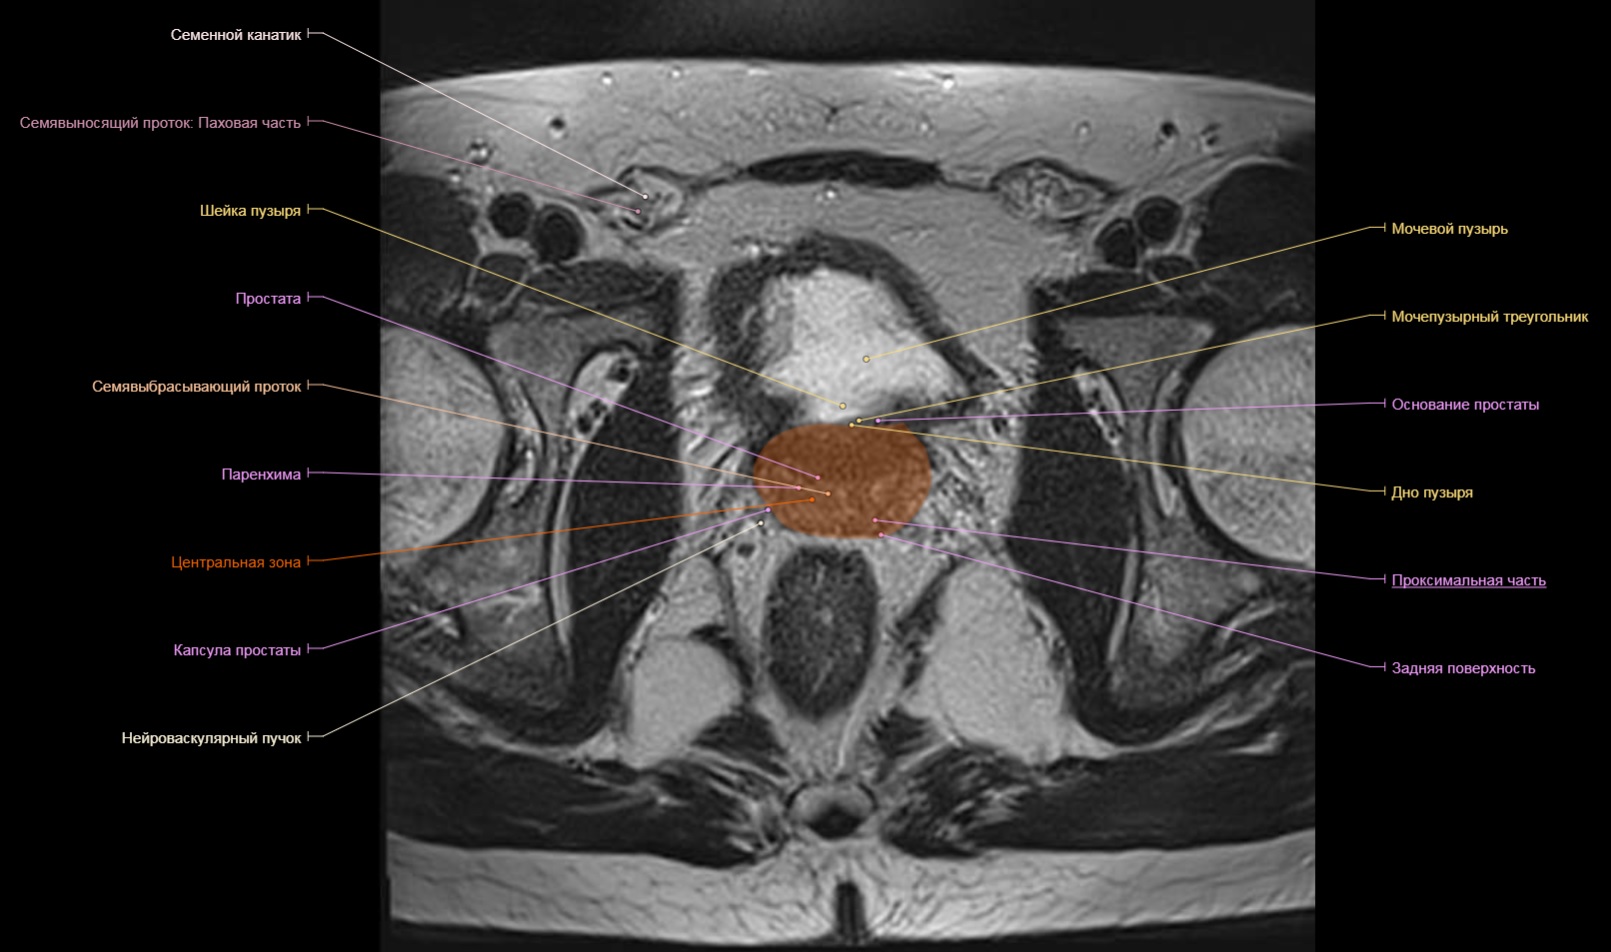

Аденома предстательной железы мрт

Шейка мочевого пузыря мрт анатомия

Предстательная железа MRT

Аденома предстательной железы мрт